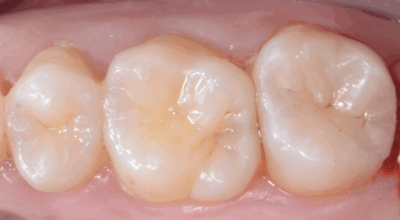

Cas clinique

Pulpotomie partielle : 88,2% de taux de succès